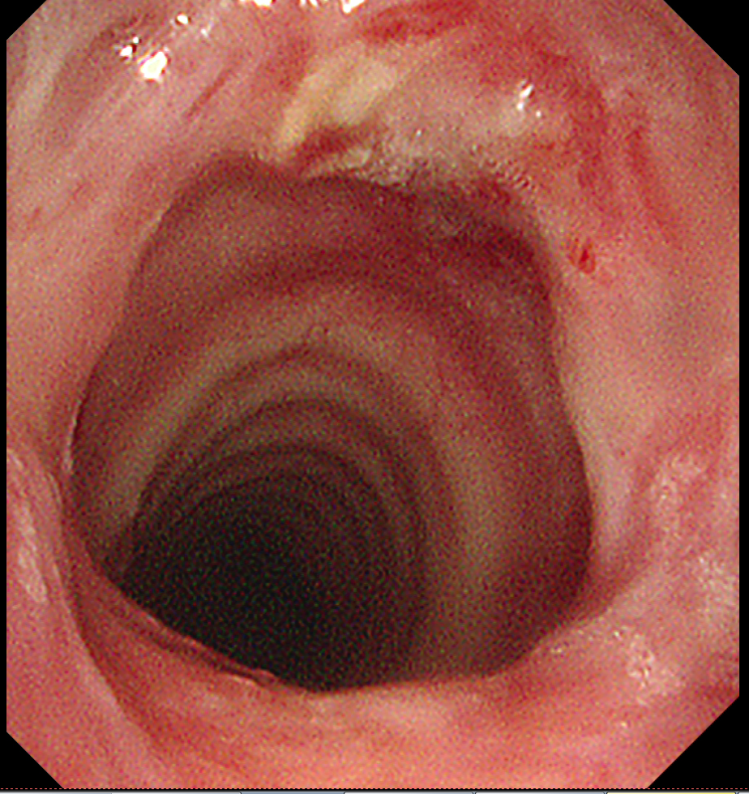

当谢先生从麻醉中苏醒,立即感受到呼吸的畅快——困扰他许久的憋闷感消失。得益于微创技术创伤小、恢复快的优势,他在术后第二天便顺利出院。一周后,谢先生返院接受第二次纤支镜介入治疗巩固疗效。复查显示,其气道狭窄程度已从80%改善至20%,接近正常水平,呼吸功能基本恢复如常,如今已能自由活动,回归正常生活。